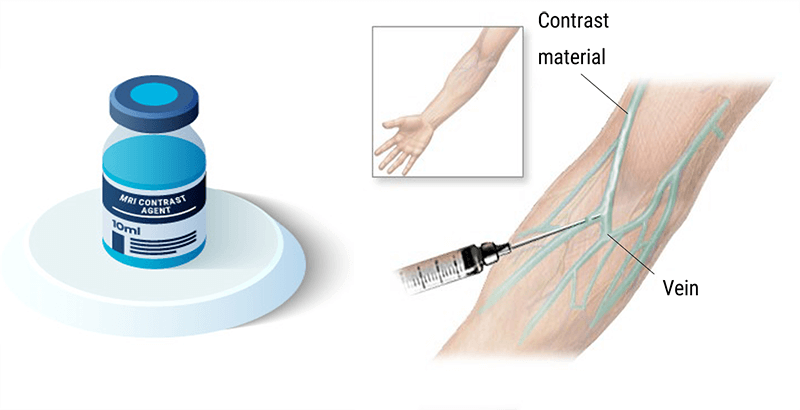

MRI contrast is used in about 1 in 3 MRI exams. MRI contrast, like other contrast, provide additional information and clarity in the images. It allows us to see information about organs and structures that may not be visible without contrast – and provides differentiation between tissues. Contrast aids in the diagnosis of certain types of pathologies and conditions and allows us to see vascular structures better. Not ALL exams require the use of contrast, but many do. Gadolinium is used to increase the T1 relation of tissue and is the most common contrast used in MRI. We will learn more about Gadolinium on the following slides.

Intravenous Contrasts

The contrast used in MRI is made of Gadolinium. Gadolinium is a metal of the Lanthadines chemical series on the periodic table of elements. The Lanthanide series consists of the transition metals located between the elements of atomic numbers 57 (La) to 71 (Lu) all included. They are also known as rare earth.

Gadolinium has 64 electrons. The size of a gadolinium ion Gd3+ competes with calcium and thus can block the reticuloendothelial system. It competes with calcium at the levels of myocardial contraction, coagulation, calcium-dependent enzymes, mitochondrial respiration, and neurotransmission. For this reason, Gadolinium is the particularly toxic element in its free state. This is why we use it as gadolinium, chelate bound to a linear or cyclic molecule.

Osmolality

Osmolality refers to the number of particles present in a solution. Blood has an osmolality of 275-295 mosm/kg. Any solution with a higher osmolality than blood is considered hyperosmolar. Gadolinium has an osmolality of 630-1970 mosm/kg. The injection of a hyperosmolar product provokes a call for water from the interstitial to the interior of the vessel: this provokes hypervolume expansion.

The venous system is a capacitive system and it dilates easily causing a heat sensation. The arterial system is a resistive system, the vessel does not dilate easily, which causes a painful feeling.

In MRI, the amount of a substance given to the patient is very low and most of the time, the patients do not feel anything. But, it is always safe to use contrast with the lowest osmolality possible. The information about the contrast used in your facility can be found on the package insert with the contrast.